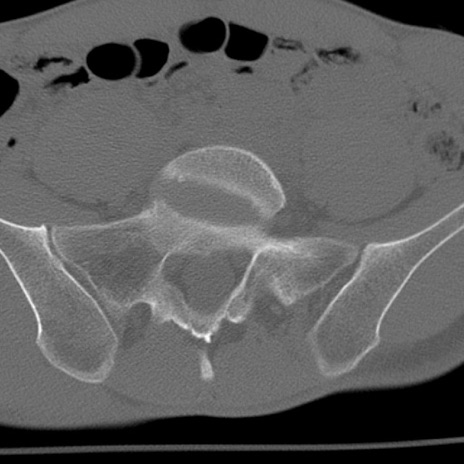

症例3 腰椎CT(横断像)

腰椎CT